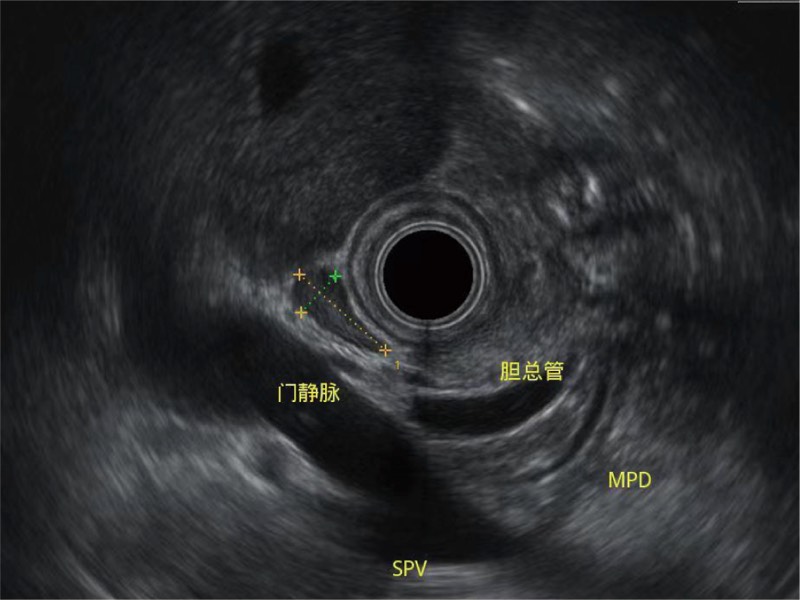

清晰显示胆总管及周围血管分布